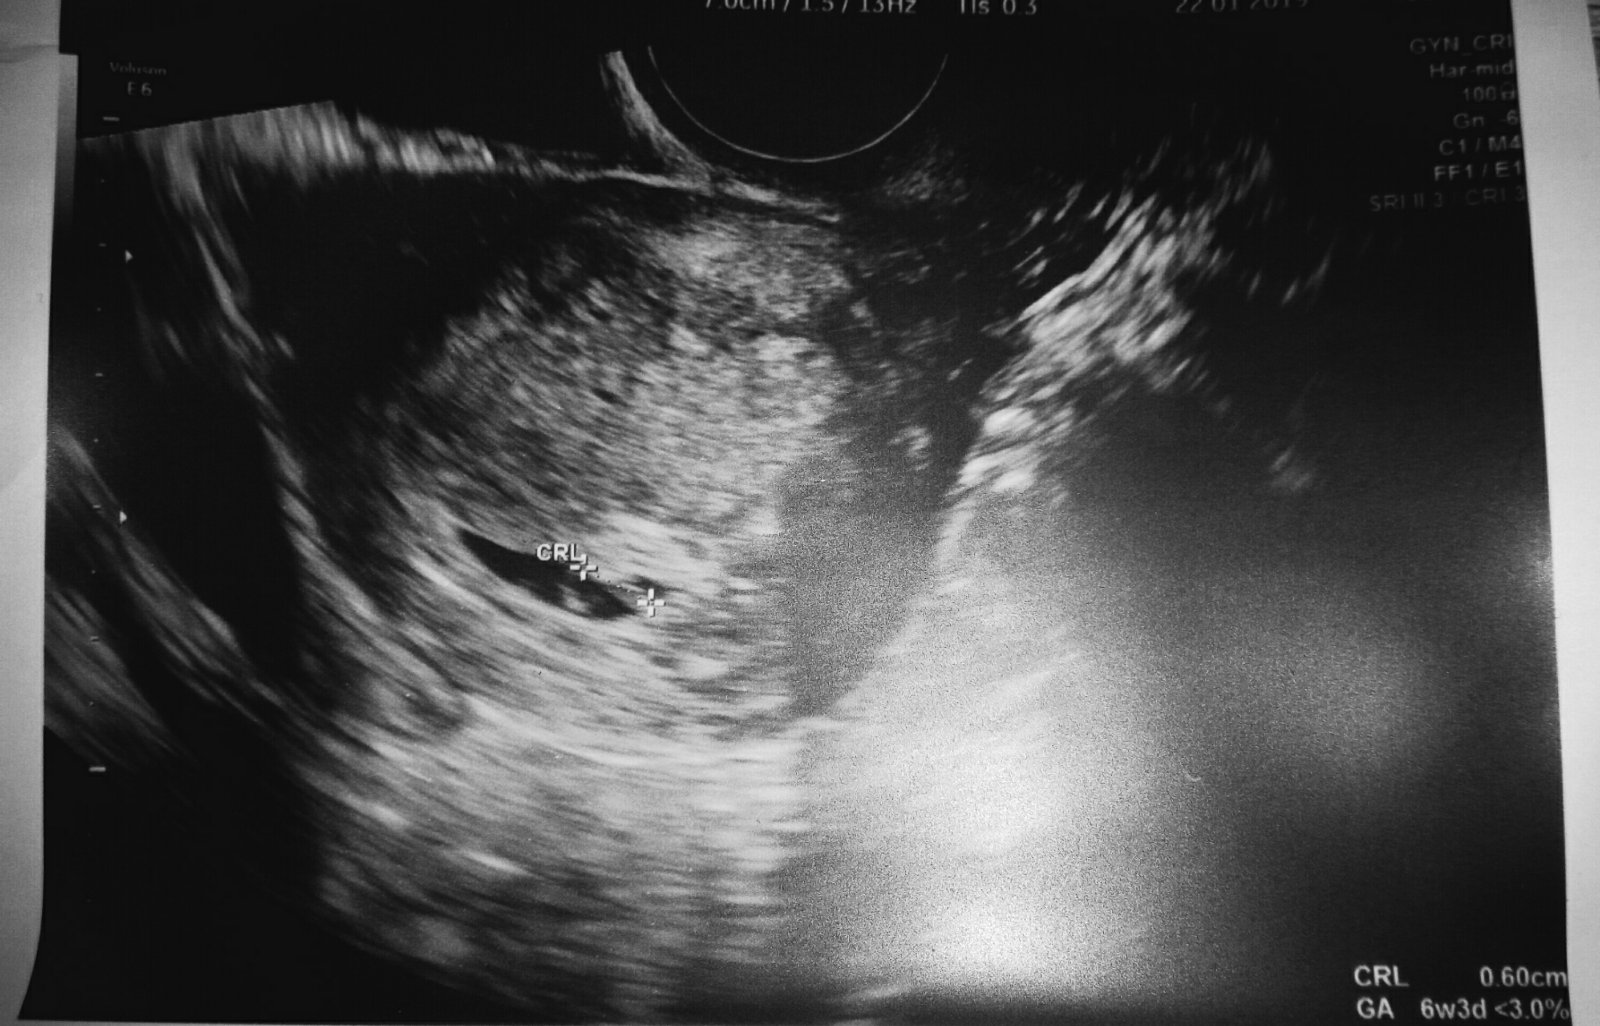

@saminomimino ten druhy? 🙂 Ano a dnes mi vysli dva rozne testy so slabou ciarkou skusala som rano a teraz 5 min dozadu a je jasnejsia ako rano 🙂 tak asi tento cyklus bol ten spravny 🙂

@sudylichozrout ďakujeme 🙂 .. teraz už len dúfať že pôjde všetko tak ako má 🙂